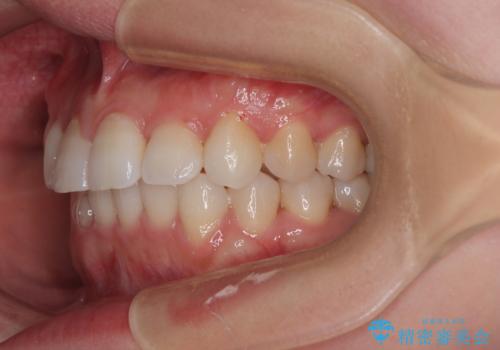

捻転の強い前歯 ワイヤー装置での非抜歯矯正

- 前歯のデコボコ、特に90度捻れている上顎前歯を気にして来院された患者様です。

マウスピースでもワイヤーでも対応可能でしたら、捻転が非常に強いことから、患者様と相談の上ワイヤー装置にて矯正治療を行うこととしました。

捻転を解消する際に、歯列全体が前方に突出して出っ歯の仕上がりとなることが懸念されたため、補助装置を用いて上顎歯列全体を後方に移動する力をかけることとしました。

当初予定通り1年半ほどの治療期間で、非常に綺麗な歯列に仕上げることができました。